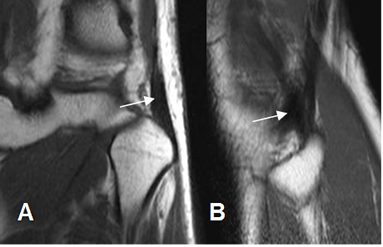

Los componentes del complejo de la esquina posterolateral, son mejor identificados en secuencias coronales y sagitales, por detrás del tendón poplíteo. (4). (Fig 21 a 28).

Fig 21. Tendón del bíceps femoral normal.

A: RM coronal en T1 y B: RM sagital en T1. Tendón normal, insertándose en la cabeza del peroné.

Fig 22. Esquina posterolateral normal.

A: RM coronal y B: RM sagital en T1. Inserción conjunta en la cabeza del peroné del LCL (Flecha delgada) y el biceps femoral (Flecha gruesa).

Fig 23. Tendón poplíteo normal.

A: RM coronal en STIR y B: RM sagital en T2. Tendón poplíteo normal, originado en el cóndilo femoral lateral.